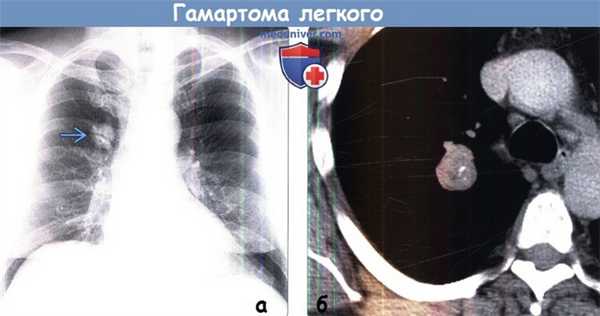

(а) Некурящий пациент 56 лет с жалобами на кашель. При рентгенографии органов грудной клетки в ПП проекции над корнем правого легкого определяется узелок с четким контуром размером 2,6 см . На рентгенограмме кальцификаты не видны.

(б) У этого же пациента при нативной КТ визуализируется узелок с четким дольчатым контуром, который содержит как макроскопический участок жировой ткани, так и грубые кальцификаты. Была выполнена резекция узелка, и было показано, что он соответствует гамартоме легкого. Несмотря на то что данная опухоль является доброкачественной, при наличии симптомов может быть выполнено хирургическое лечение.